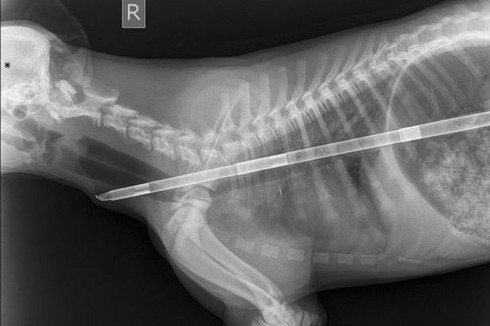

Chú chó được cứu sống sau khi nuốt vật thể dài gần nửa mét. Nguồn: Mirror |

Bác sĩ Garland đã thực hiện một ca phẫu thuật khẩn cấp để cứu chú chó. Ông đã thực hiện cắt thực quản để loại bỏ dị vật đang nằm trong người con vật, có đường kính khoảng 1,2 cm.

Ông cho biết đây là vật thể “kỳ lạ nhất” mà ông đã từng lấy ra từ bụng một con thú cưng.